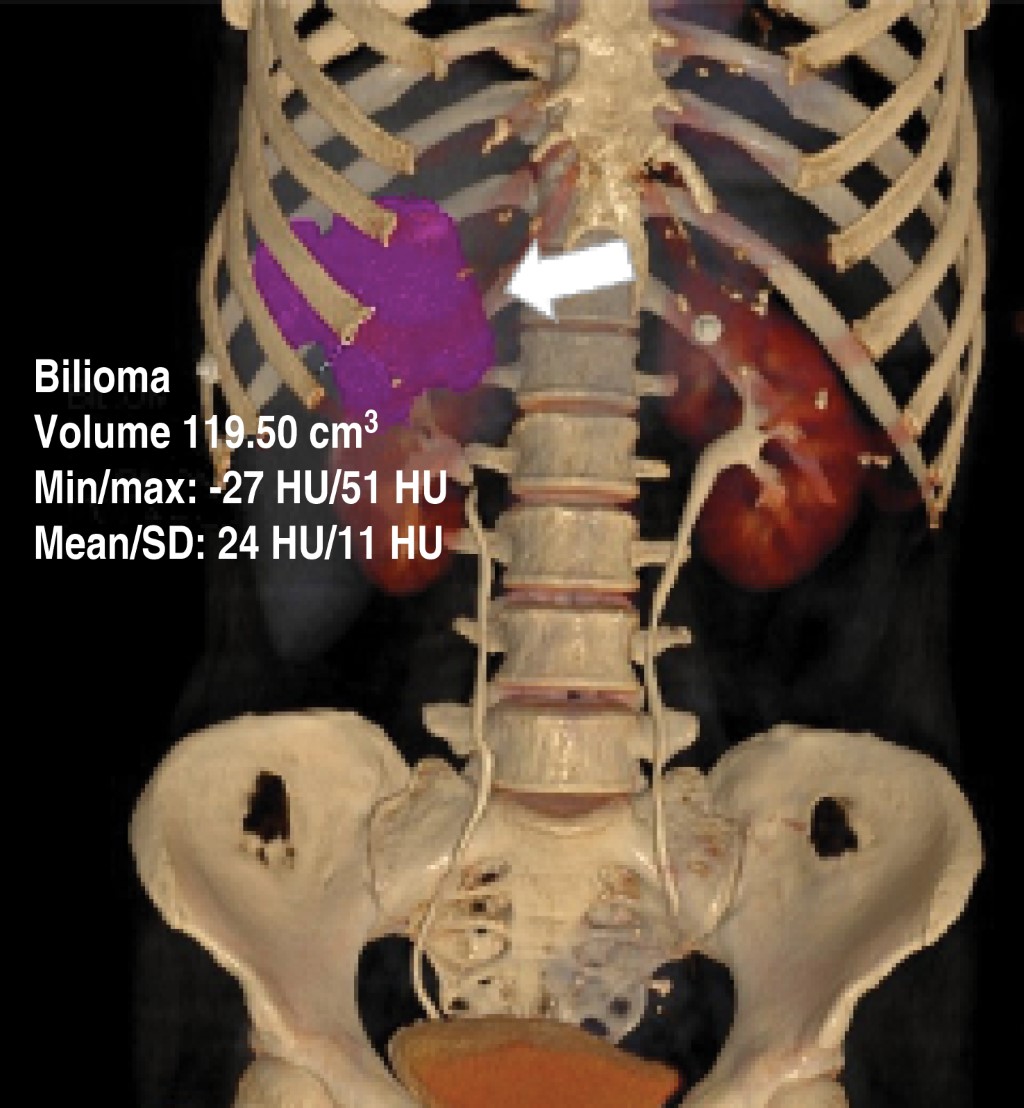

A 55-year-old female patient came to the emergency department with a picture of a month of evolution characterized by abdominal pain located in the epigastrium and right hypochondrium, radiating to the interscapular region, which was increasing, so she decided to go to the doctor who started homeopathic treatment; however, she did not improve, so she went to the emergency department of our hospital unit where the following vital signs were recorded: BP (blood pressure) 114/76 mmHg, HR (heart rate) 124 bpm, RR (respiratory rate) 16/min, and temperature of 36 °C. On questioning, the patient denied the presence of fever, nausea, vomiting, or the presence of bowel movements of decreased consistency. For her approach, general laboratories were requested, highlighting the presence of leukocytosis (12,300 mm3), elevated alkaline phosphatase, and GGT (315 and 268 U/l respectively); a CT scan of the abdomen with intravenous contrast was requested (Figures 1, 2 and 3) which showed the presence of gallbladder with impacted lithos in its interior, and an intrahepatic rupture, in addition to an intrahepatic abscess in segments IV and V (Figure 2).

Figure 1